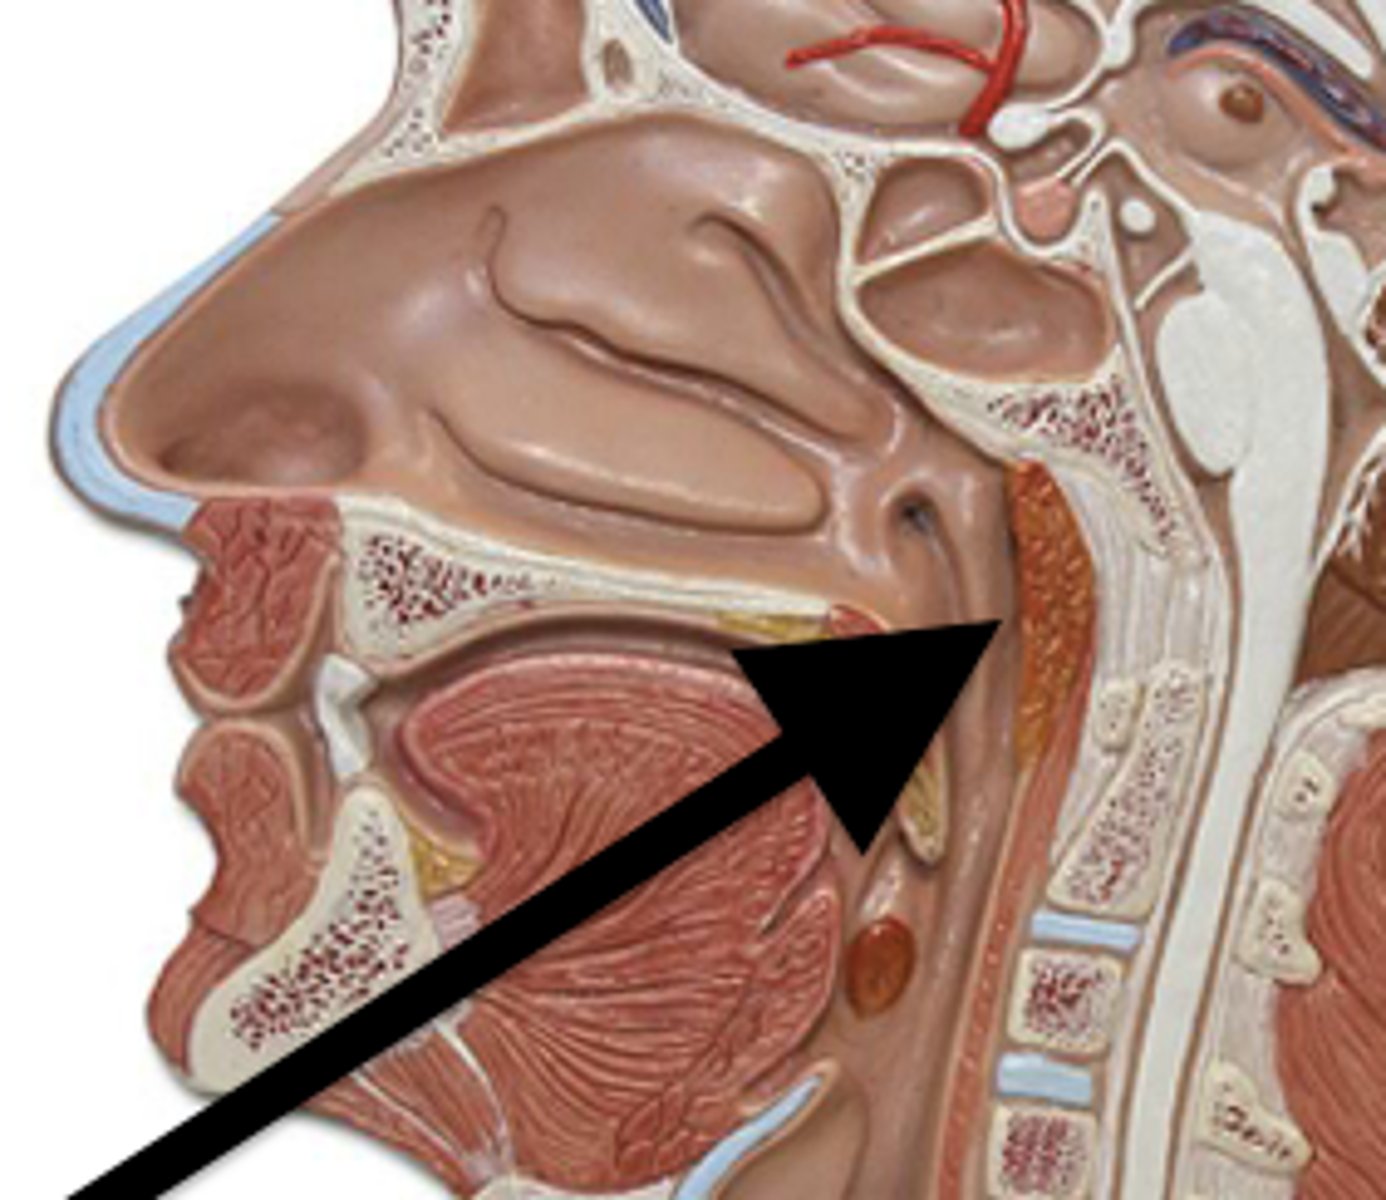

tonsils

form a ring of lymphatic tissue around the openings to the pharynx.

pharyngeal tonsils (adenoids)

sits on the posterior wall of the superior pharynx. This location allows it to filter inhaled air for pathogens.

palatine tonsils

are found on the lateral walls of the oral portion of the pharynx (the oropharynx). These tonsils are in prime position to "catch" pathogens being ingested with food.

lingual tonsils

reside on the superior surface of the posterior tongue. These tonsils are in prime position to "catch" pathogens being infested with food.